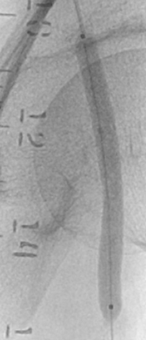

放电二个周期后

研究者观点

术中朱杰昌主任、王端医师表示“赛禾医疗冲击波外周球囊导管柔顺,即使是较为挑战的桡动脉入路,推送性表现依然很好,主机操作也很便利,学习曲线短。在执行第二个放电周期后,随即观察到腰征消失,证明了冲击波对严重钙化病变的有效性。”